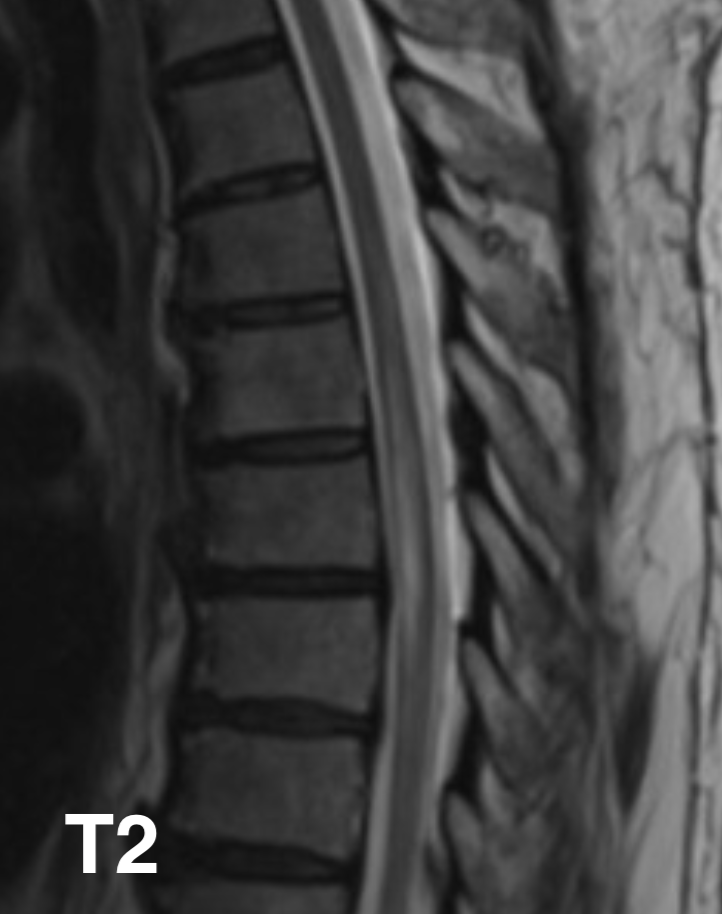

Ventral cord syndrome (also known as anterior cord syndrome) is one of the incomplete cord syndromes and affects the anterior parts of the cord resulting in a pattern of neurological dysfunction dominated by:

Ventral cord syndrome encompasses all causes of damage to the anterior spinal cord regardless of aetiology (see below).

In contrast, anterior spinal artery syndrome, also known as Beck’s syndrome, denotes a ventral cord syndrome specifically due to ischaemia/infarction of the anterior two-thirds of the spinal cord due to involvement of the anterior spinal artery.

Involvement of the anterior half to two-thirds of the spinal cord results in a predictable pattern of neurological impairment consisting of:

Importantly 2-point discrimination, proprioception and vibratory senses are normal due to intact posterior columns and posterior grey matter.

Ventral cord syndrome is caused by a variety of processes, the most common one being ischaemia due to occlusion of anterior spinal artery, which in turn is the result of a number of underlying processes. As such, the list of causative pathologies is very similar to that of acute spinal cord ischaemia syndrome.